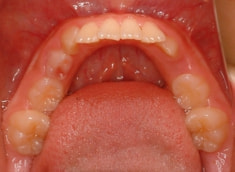

治療前

治療後(12ヶ月後)

上顎の劣成長が顕著なので、上顎犬歯の萌出するスペースが不足しています。

また、統計通り、左上の犬歯です。